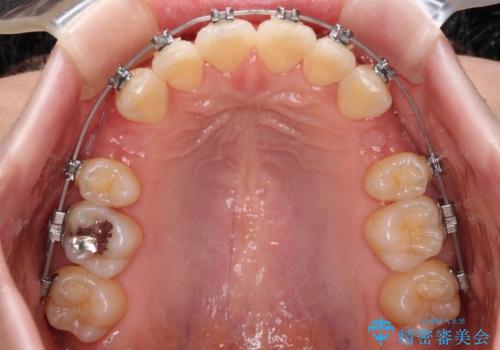

- メタルブラケット

- 2年2ヶ月

- 10-30回